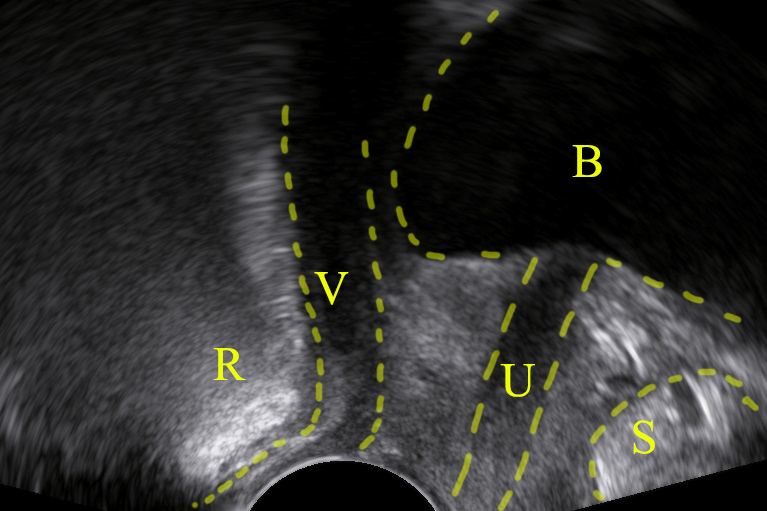

Depicting a rectocele in pelvic floor ultrasound is feasible: